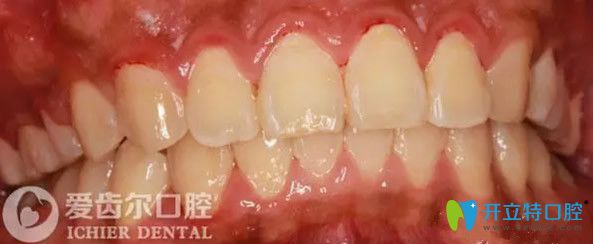

經(jīng)過12個月的治療,我成功摘除了托槽與弓絲,牙齒擁擠的情況得到了明顯的改善,牙齒已經(jīng)排齊,咬合關(guān)系良好,達到了我預(yù)期的治療目標(biāo),對矯治效果很滿意。

一年后的效果圖:無論從哪個方向看,我的牙齒都很整齊。

自鎖托槽矯正牙齒一年后